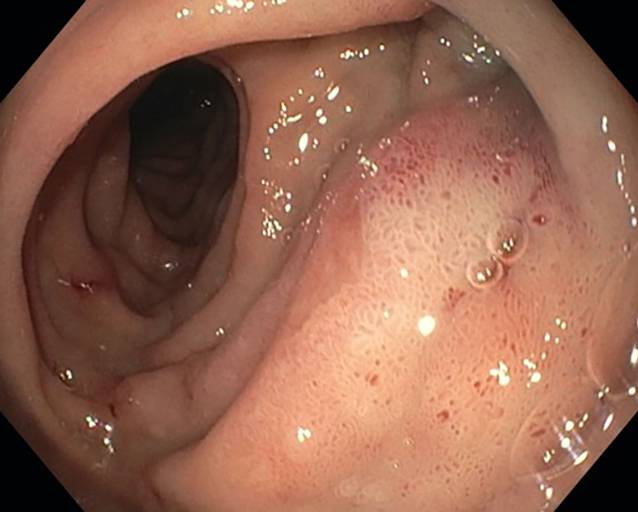

Nach 5 Tagen wurde der Patient aufgrund des klinischen Verdachts auf eine Fehllage des Nephrostomiekatheters notfallmäßig vorstellig. Über den Katheter entleerte sich galliges Sekret. Schmerzen bestanden nicht, auch kein Fieber oder eine Makrohämaturie. Laborchemisch bot sich kein Anstieg der Infektparameter. Sonographisch fand sich das NBKS rechts zweit- bis drittgradig ektatisch, links ungestaut. Nativ-röntgenologisch in einer Ebene zeigte sich die Nephrostomie von rechts mit Ende in Projektion auf das Nierenbecken auf Höhe des rechten Querfortsatzes LWK 1 (Abb. 1).

Abb. 1

Einliegender Nephrostomiekatheter, Röntgenleeraufnahme zum Aufnahmezeitpunkt